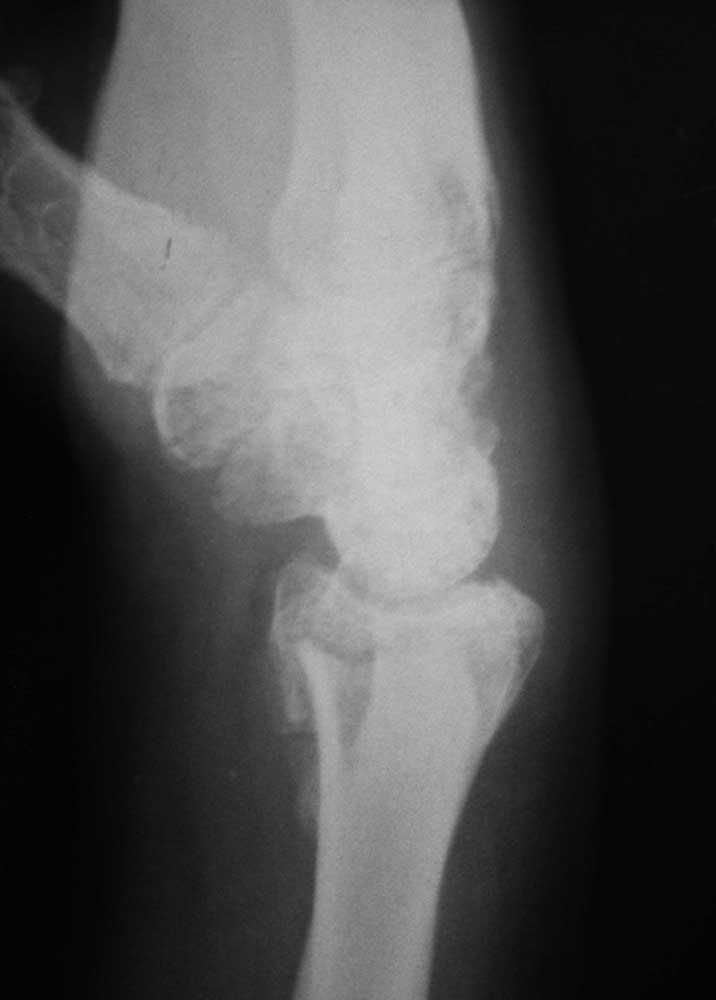

Re: Перелом дистального луча

То же самое, только в профиль

боковая и косая полупронированная проекции